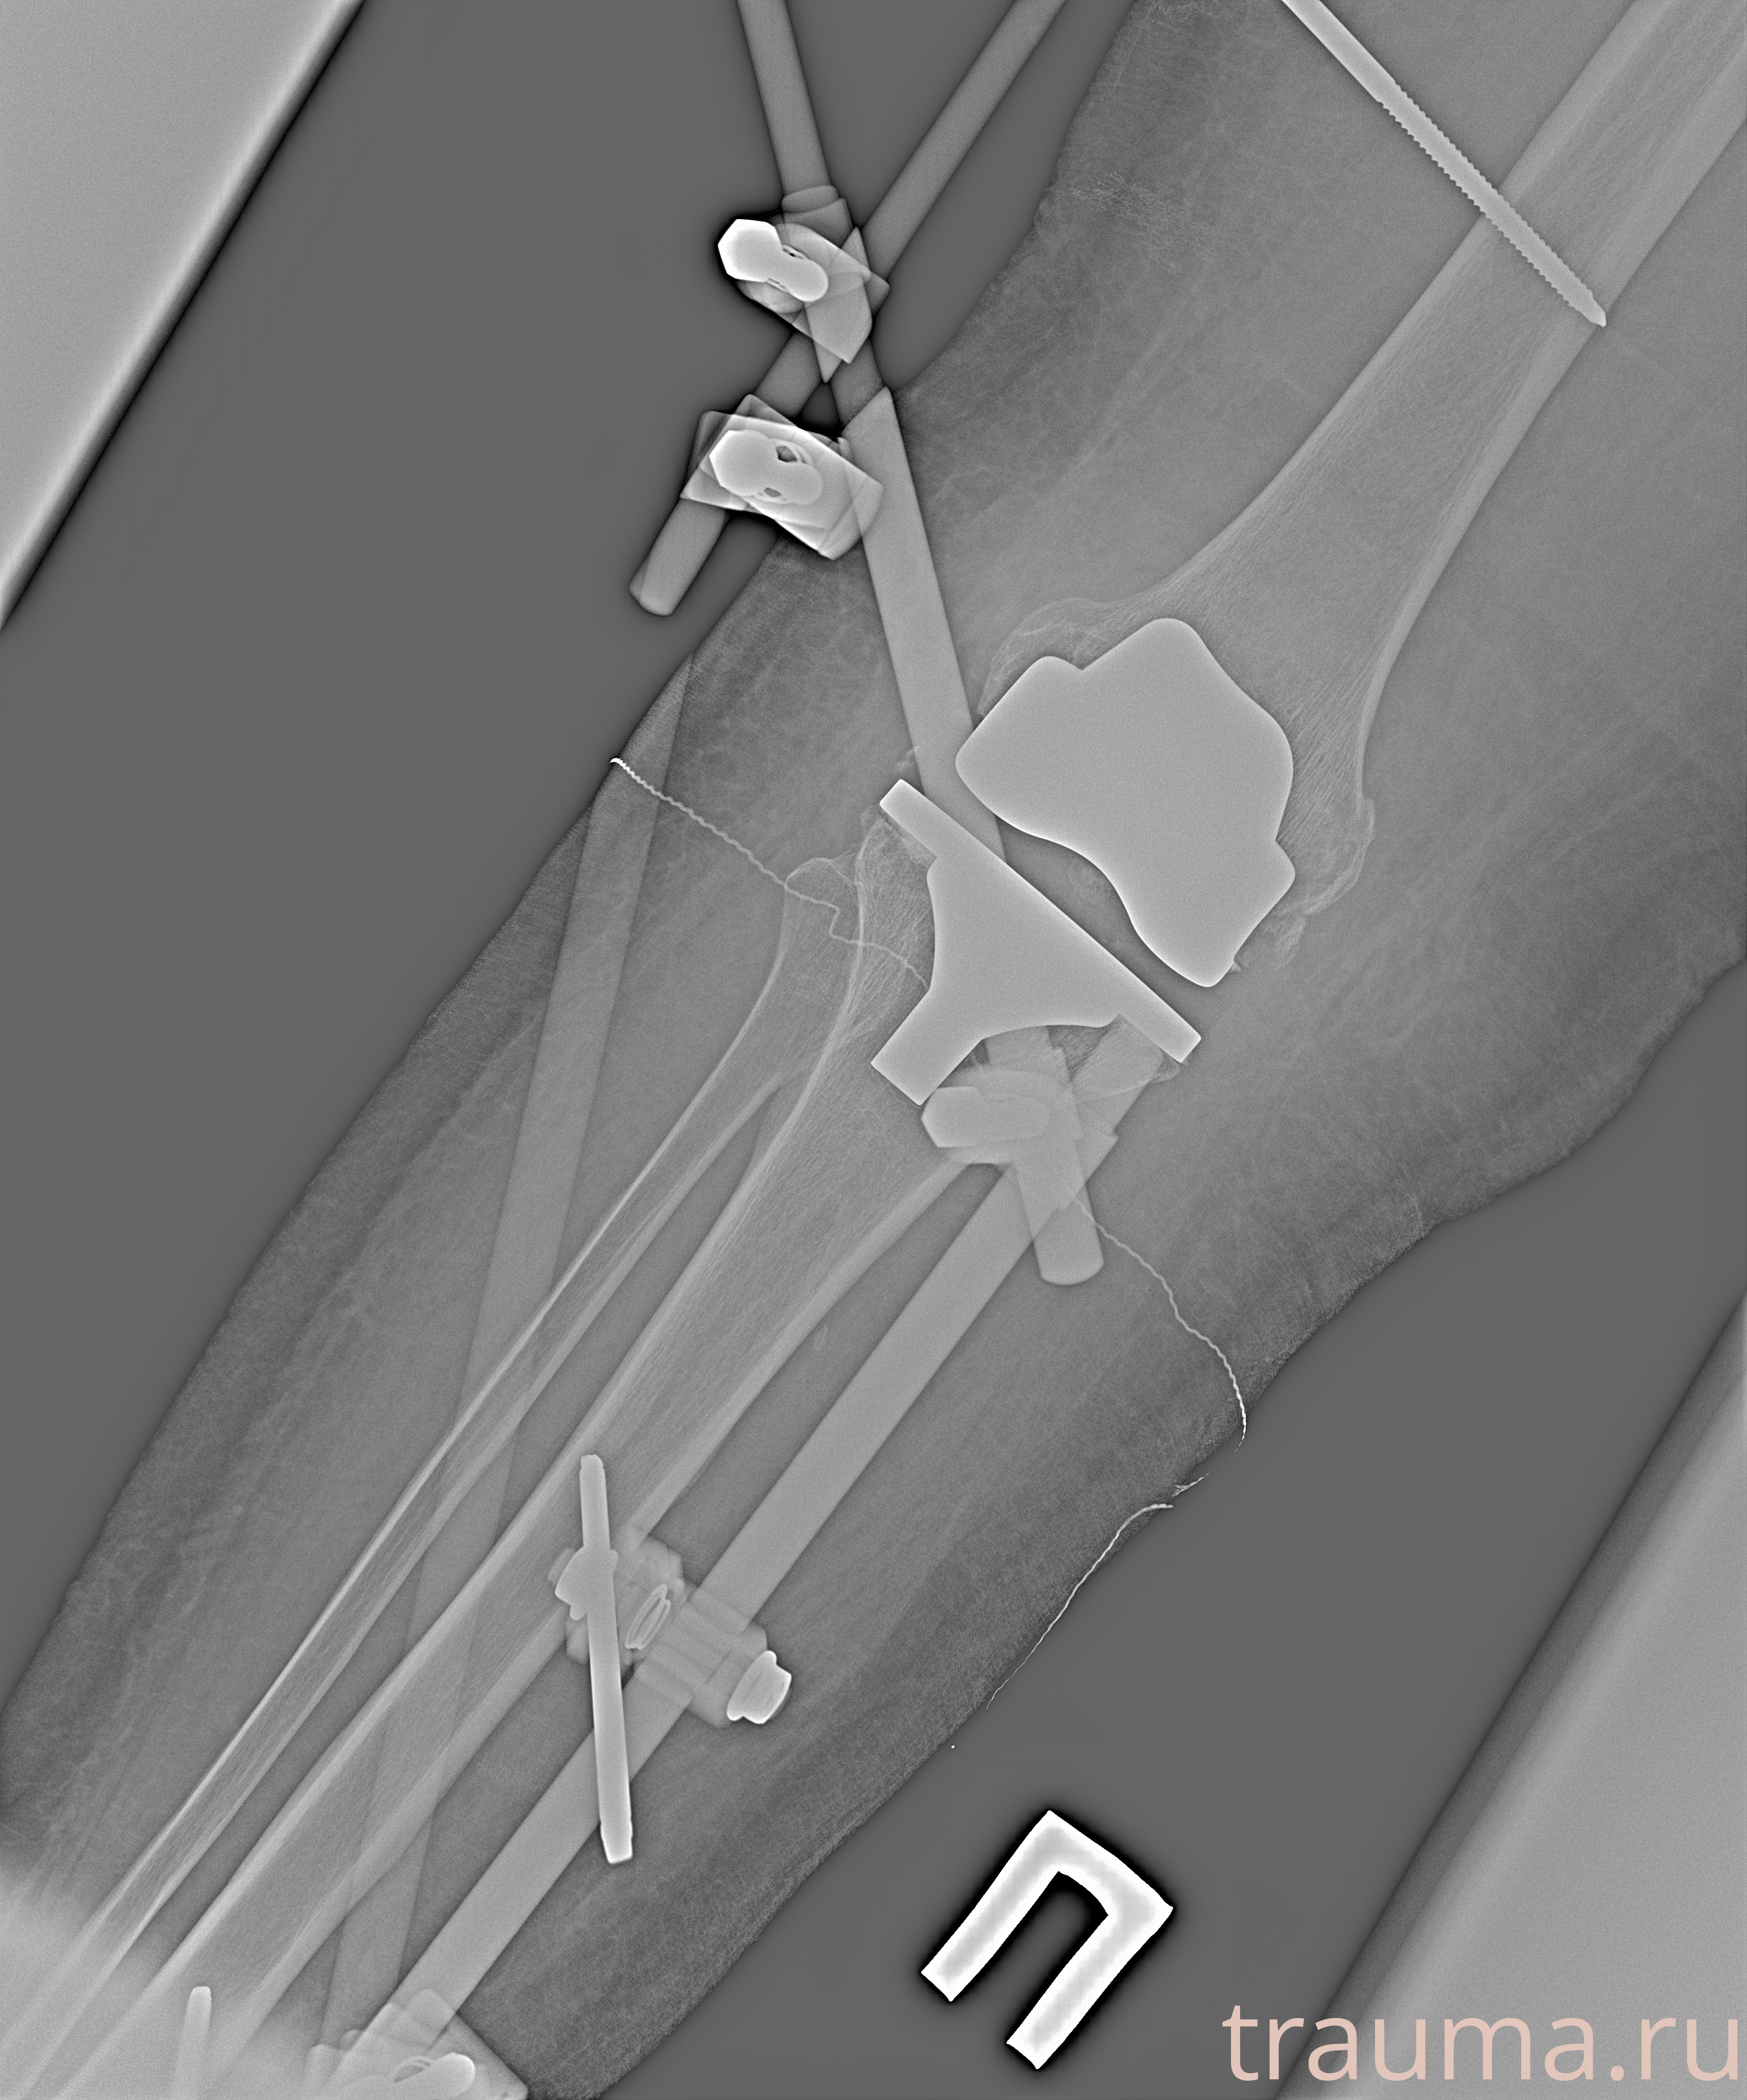

Рентген на дому: по вашему адресу приезжает врач-рентгенолог, травматолог-ортопед с мобильным рентгеновским аппаратом, проводит диагностику травмы или заболевания, делает необходимые рентгенограммы, дает рекомендации по дальнейшему лечению. Получить качественные снимки в домашних условиях возможно благодаря уникальной методике, разработанной МосРентген Центром для института  Склифосовского

Видео КТ после вправления и наложения АНФ